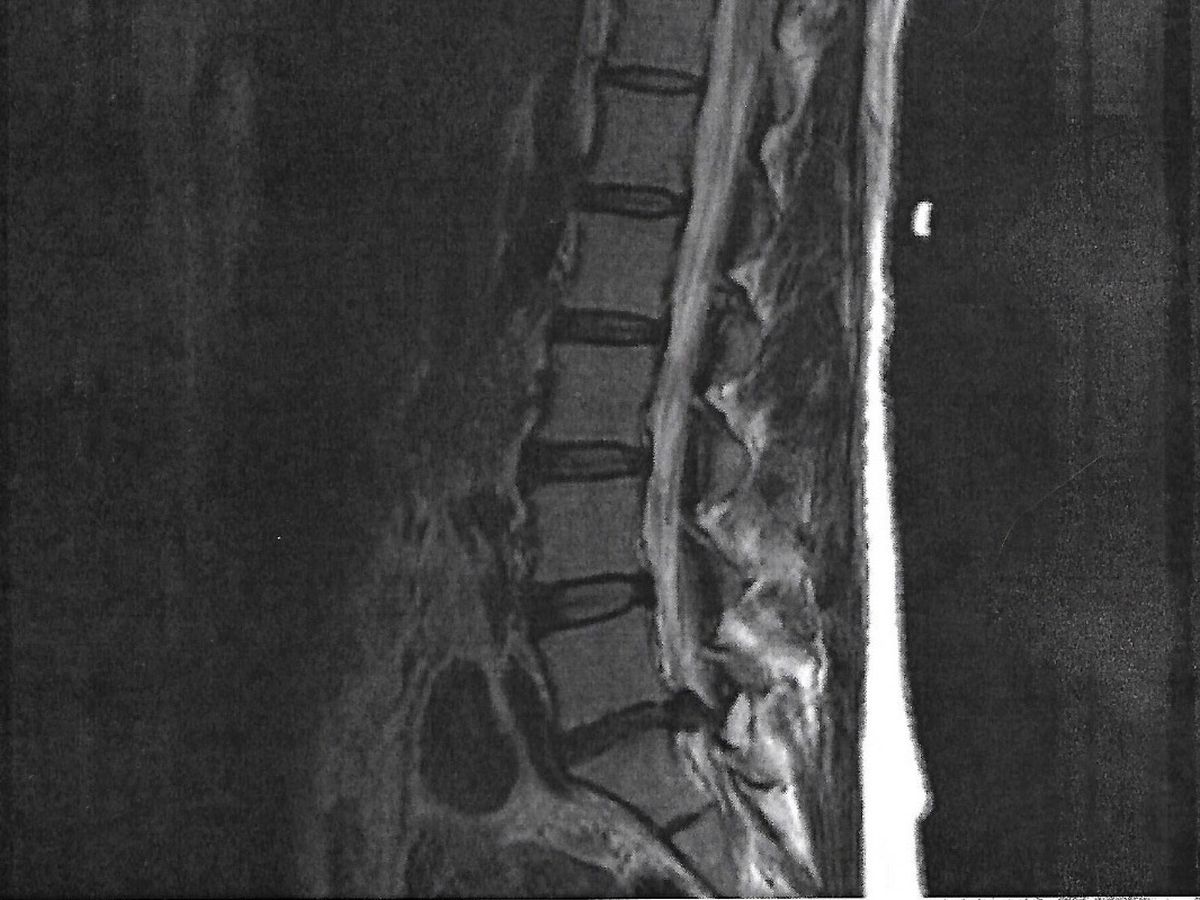

For the third time in four months, I will be having major surgery. I have a massive L5-S1 disc herniation that is so severe I’ve lost most function and sensation of my left foot and leg. Without surgery, the herniation will not heal on its own and would leave me permanently disabled. With surgery, I should make a complete recovery in about four weeks. Even with short term disability through work, when I return I will not have any vacation or PTO to use if I need time off for any reason. I will likely lose my job because of this injury. If you are able to help in the coming weeks of my recovery, I would appreciate any assistance I can get - rides, meals, visits or funds. My medical costs over the last four months are now one third of my yearly income and I may be without work in a month. I have a son to support and no parents or siblings to help. Please spread the word. Thank you from the bottom of my heart.